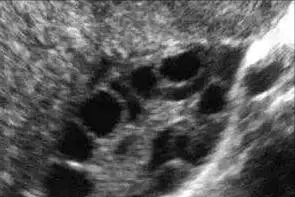

平时看门诊的时候常常有病人会问我,医生,为什么你要给我在月经期做阴道B超检查呢?经期不是不能做检查的吗?每当这个时候,我都会耐心地跟她解释,月经期第二至第四天的经阴道超声检查的目的,是为了测量双侧卵巢直径2~10mm的小卵泡(也叫窦卵泡)的数目,这是一项评估卵巢储备功能的重要而且比较可靠的检查方法。那么什么是卵巢储备功能,它有什么重要的意义呢?

卵巢储备功能是指卵巢皮质区内的卵泡生长、发育形成可受精卵子的能力,包括卵巢内存留卵泡的数量和质量,它反应了女性的生育潜能。卵巢储备功能不良是指卵巢内存留的可募集卵泡数目减少,卵母细胞质量下降,可导致生育能力降低或出现过早绝经倾向。一般女性在出生时体内大约有200万个原始卵泡,到初次月经的时候只剩下20万~30万个,自此之后,每个月会减少几百个,一生中大概只有400~500个卵泡能够发育成熟并排卵,随着女性年龄的增长,卵巢内卵泡数量越来越少,直到绝经后卵巢萎缩。目前由于外界不良环境的不断刺激、基因突变或染色体变异的不断增加、卵巢手术、肿瘤放疗及化疗、心理因素等的影响,卵巢储备功能不良有逐渐增多及年轻化的趋势。那么除了经期阴道超声检查卵巢窦卵泡这一评估卵巢储备功能的最佳单一指标外,还有什么其他的指标呢?